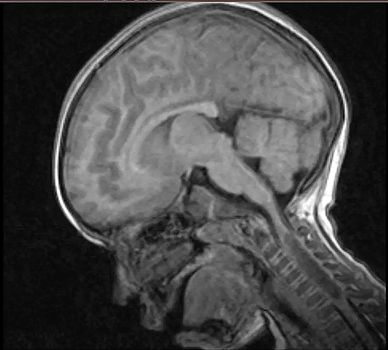

This 4-year-old-girl from Venezuela presented with severe neck pain and weakness on the left side of her body. Imaging studies revealed a space-occupying lesion involving her cervical spine.

Given the imaging results, a biopsy was performed, and the tumor initially interpreted as a grade 2 astrocytoma. The specimen was sent to Dr. Zambrano's team for additional review.

In view of these results, the tumor was reclassified as a pediatric-type high-grade glioma (courtesy of Dr. Daniel Marker, UPMC Neuropathology Center of Excellence) and the specimen was submitted for additional methylomic studies.

Methylation profile indicated a match to diffuse midline glioma H3 K27M mutant with a high confidence score, and the tumor was classified as a diffuse midline glioma, H3 K27-altered, CNS WHO grade 4.

Following reclassification of the tumor from a grade 2 to a grade 4 malignant neoplasm, the patient’s treatment protocol was modified, and radiotherapy was added.